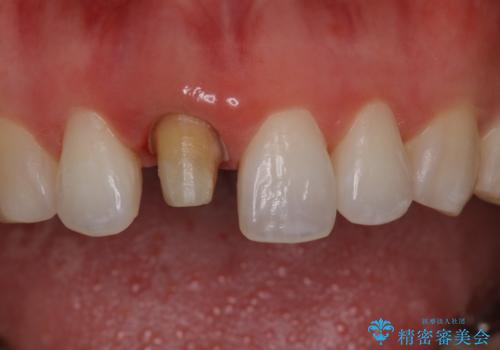

前歯の色が気になる オールセラミッククラウン(SP)

- 仮歯で矯正治療を行い、治療終了したためセラミックにて最後仕上がりをきれいにされたいという患者様の症例です。

矯正の時使用していた仮歯を新調し、その後最終的な形を作ってから型取りを行います。

色もきれいだと患者様も満足されておりました。